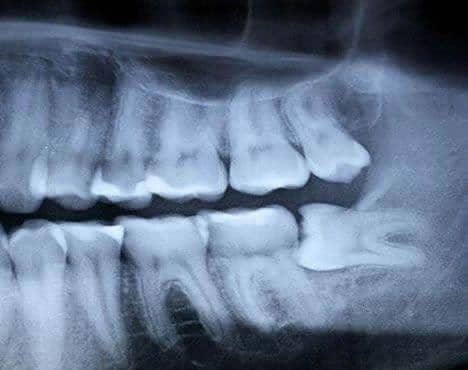

Sebelum terlambat, kita bisa melakukan pencegahan. Pergilah ke dokter gigi dan lakukan rontgen secara berkala untuk mengetahui keberadaan wisdom teeth kita.

X-ray bisa dilakukan untuk mengetahui posisi di mana wisdom teeth akan tumbuh. Gak jarang, posisi tumbuh gigi ini tak beraturan dan memberi tekanan pada gigi lain.

Sebelum masalah timbul, dokter gigi bisa merekomendasikan agar gigi ini dicabut. Pencabutan akan lebih mudah saat kita masih muda, karena akar giginya belum sepenuhnya tumbuh dan belum terlalu mencengkram gusi, terang laman Web MD. Ketika kita lebih tua, pencabutan akan lebih sulit dan pemulihannya akan lebih lama.